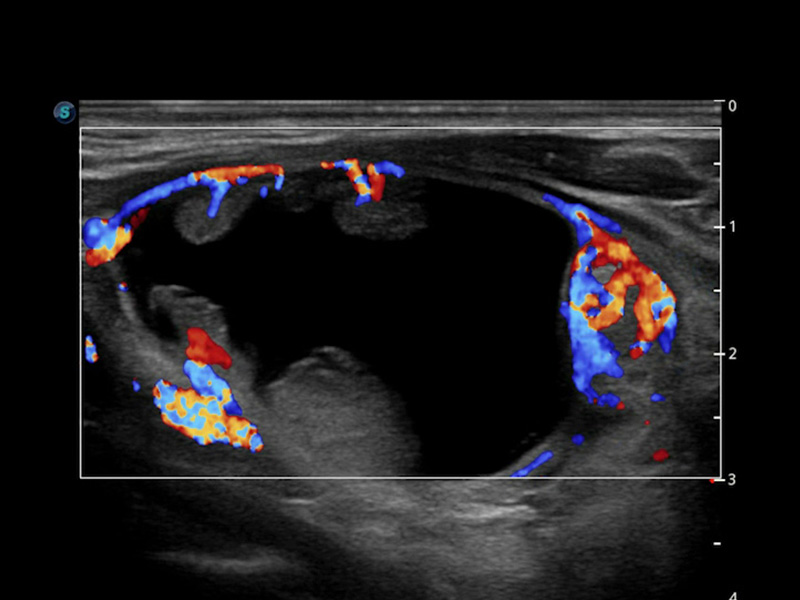

S-Thyroid

S-Thyroid*

S-Thyroid è uno strumento avanzato per il rilevamento e la classificazione delle lesioni sospette della tiroide, in conformità con le linee guida ACR TI-RADS (American College of Radiology Thyroid Imaging Reporting and Data System). Dopo aver selezionato la regione di interesse, S-Thyroid può definire automaticamente i limiti della lesione e generare un referto con le caratteristiche della lesione sospetta.

• Tumore_H: 4,58 mm

• Tumore_W: 3,71 mm

• Tumore_Area: 0,13 mm2

• Forma

Più alto che largo 3

• Margine

Lobulato o irregolare 2

• Ecogenicità

Ipoecoico 2

• Focus ecogeni

Nessuno o grandi artefatti di coda 0

• Composizione

Solida o quasi del tutto solida 2

Punti totali: 9

Consiglio: >=1,0 cm Follow

>=1,5 cm FNA